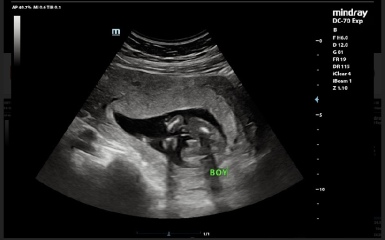

I went for a gender scan at 17 weeks and was told baby was a boy. This sonographer was confident and shared photos of baby boy.

I’ll add photos of my 17 week scan that confirmed baby was male. I’ve booked a rescan so will find out then, just curious!

Gender Scan